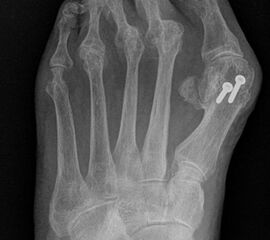

Zum Lesen der Bildbeschreibung und zur Vollansicht bitte das Bild anklicken.

Deutlich bessere Ergebnisse wurden erreicht durch eine Kombination der OP nach Tillmann mit einer Arthrodese des Großzehengrundgelenks oder auch einer Lapidus-Arthrodese 611. Dies wurde bereits 1956 durch Vainio empfohlen, hat sich aber erst in diesem Jahrtausend flächendeckend durchgesetzt 121314.